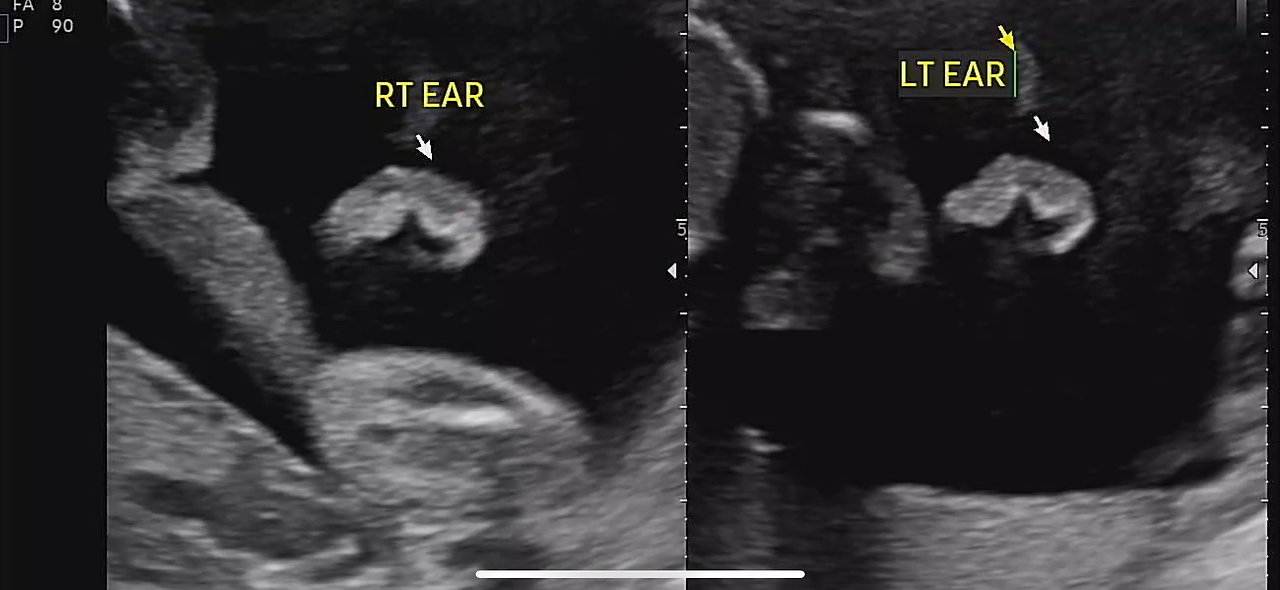

정밀 초음파는 생각보다 오래 걸렸다.

30분 가까이 이어진 검사 동안

손가락, 발가락, 귀, 콧구멍까지

아이는 하나하나 자세히 확인되었다.

22주 정밀초음파